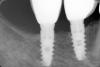

johniola Опубликовано 21 мая, 2013 Поделиться Опубликовано 21 мая, 2013 (изменено) импланты mis 4 года спустяmis.bmp Изменено 21 мая, 2013 пользователем johniola Ссылка на комментарий

АнтонТЛТ Опубликовано 21 мая, 2013 Поделиться Опубликовано 21 мая, 2013 Что оцениваем то не понял?Видимо костную ткань возле соединения имплантат - абатмент 1 Ссылка на комментарий

johniola Опубликовано 21 мая, 2013 Автор Поделиться Опубликовано 21 мая, 2013 Видимо костную ткань возле соединения имплантат - абатментда Ссылка на комментарий